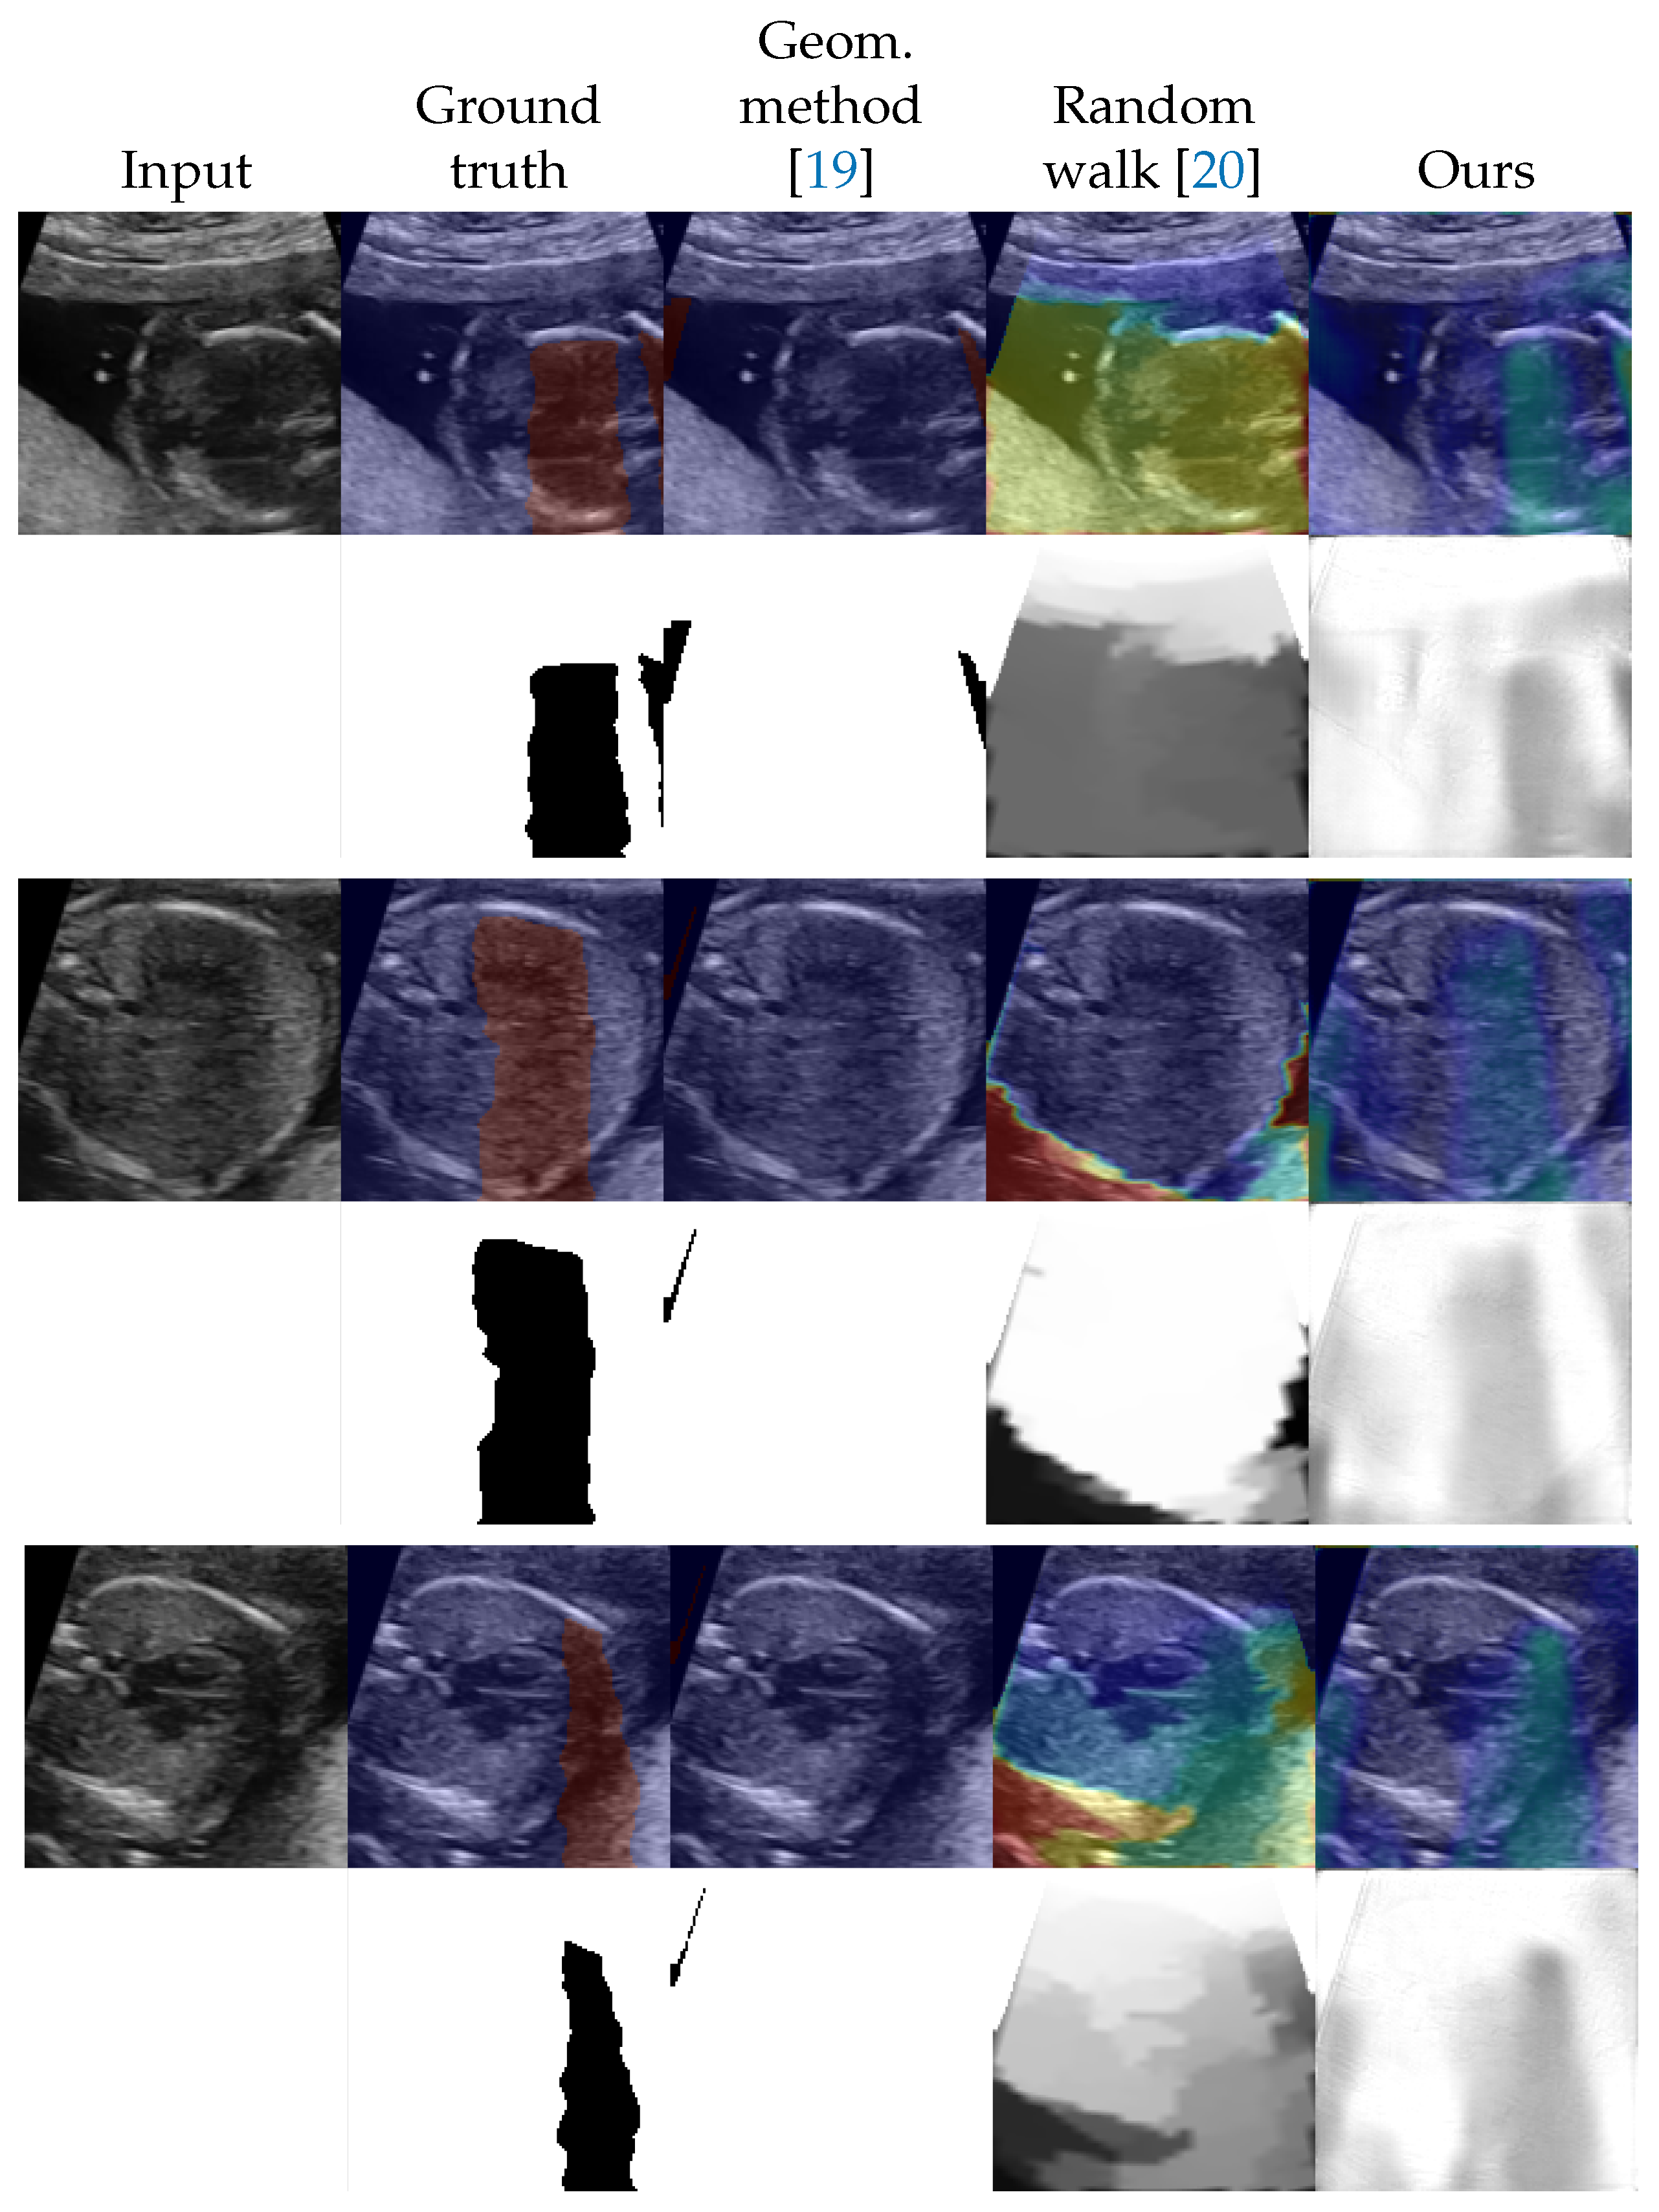

4.2. Shadow Detection

4.3. Shadow Intensity Estimation